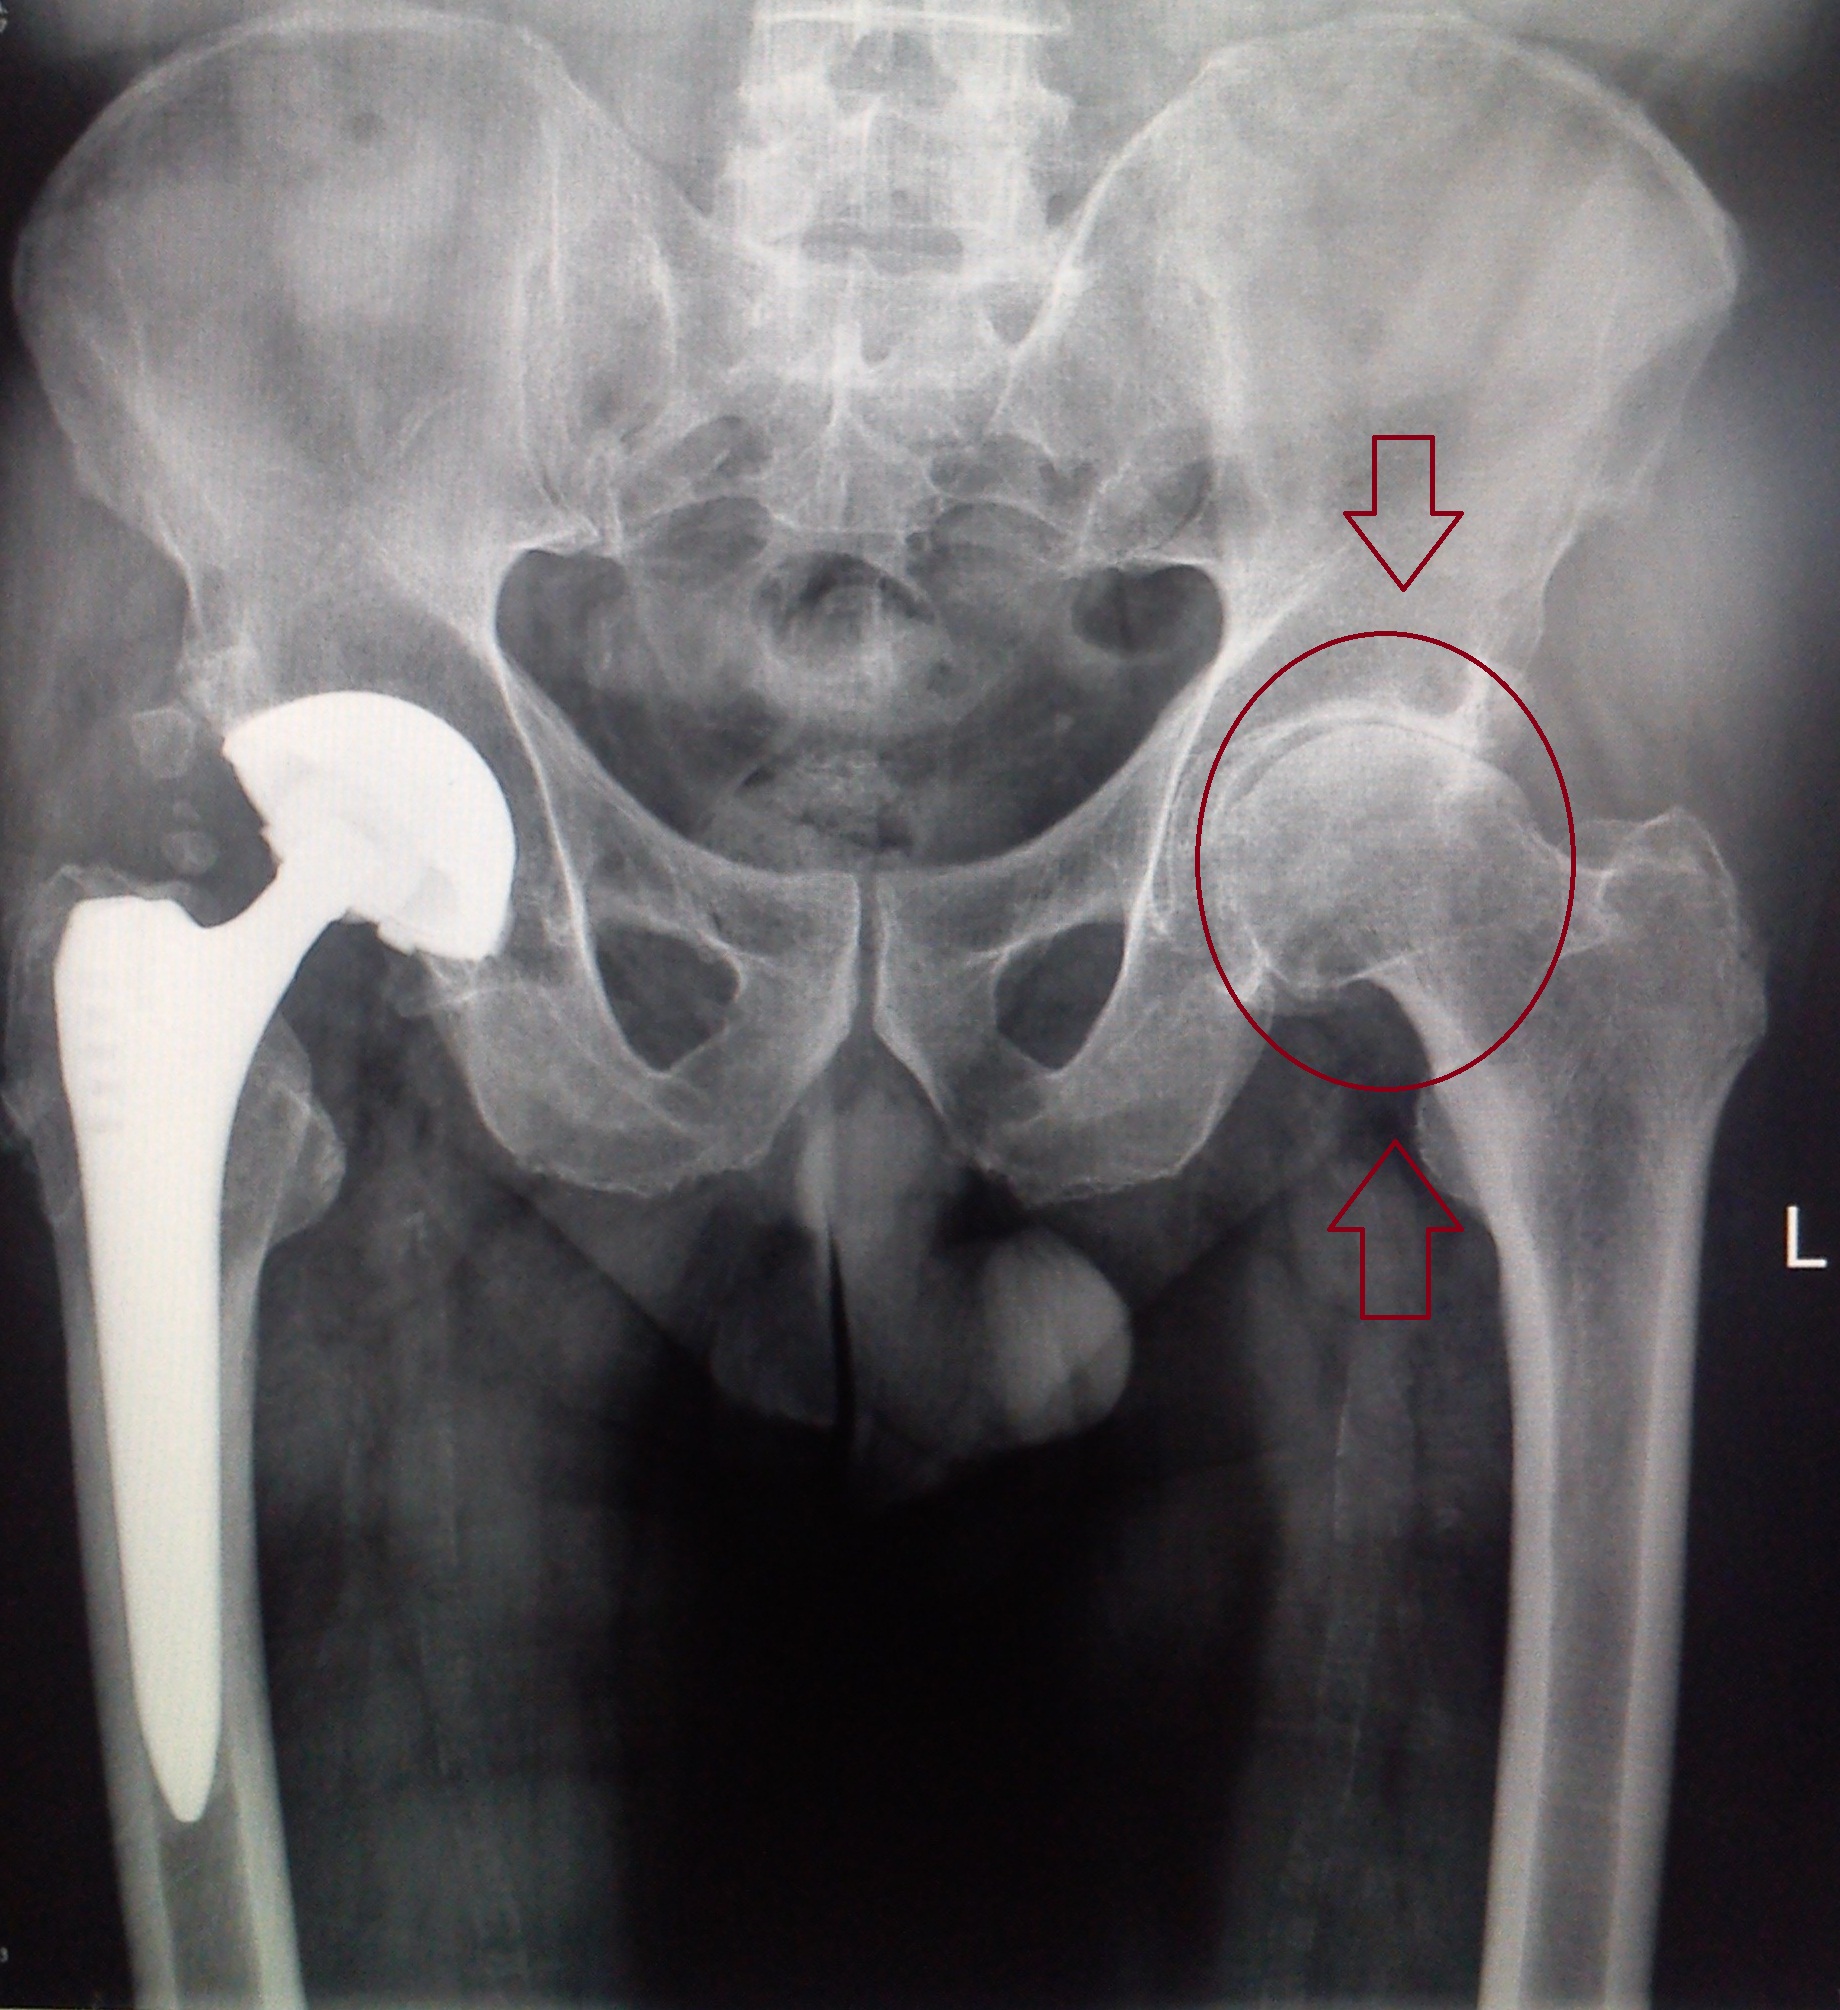

Фотографии и схемы: Коксит правого тазобедренного сустава